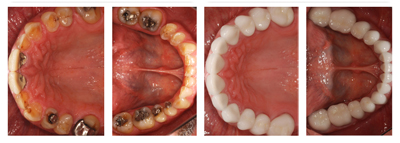

Full Mouth Rehabilitation